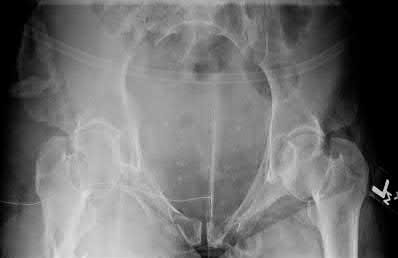

A 23-year-old female is an unrestrained driver in a motor vehicle collision, sustaining the injury shown in Figure A. She subsequently undergoes reduction and percutaneous bilateral iliosacral screw placement. Which of the following is the most likely neurologic complication associated with percutaneous iliosacral screw insertion?

Figure A shows an unstable bilateral pelvic ring injury. Percutaneous posterior iliosacral screw fixation places the L5 nerve root at risk as it courses across the sacral ala. Injury to the L5 nerve root would typically result in weakness in great toe extension and sensory changes on the dorsum of the foot. It is important to notice that L5 often partially innervates tibialis anterior along with L4, so weakness to ankle dorsiflexion may be present as well. Illustration A shows the post-operative films with bilateral iliosacral screws.

Routt et al examined the sacral slope and sacral alar anatomy in cadavers and a series of consecutive patients. They determined that the pelvic outlet and lateral sacral plain films provide the best plain radiographic views of the sacral ala. They recommended routine usage of these views intraoperatively to guide screw placement.

In another study, Routt et al reported on the early complications of percutaneous placement of iliosacral screws for treatment of posterior pelvic ring disruptions. While technically challenging, this technique leads to less blood loss and lower rates of infection compared to traditional open techniques.